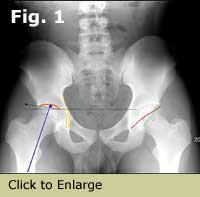

Caput valgum — superiorly placed fovea

Figure 3. Caput valgum.